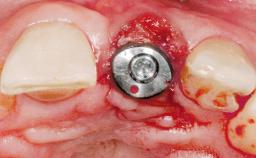

Immediate Placement of an Implant in a Maxillary Left Central Incisor Site

| Placement Protocol | Immediate implant placement |

| Tooth Site | Maxillary incisor or canine |

| Socket Morphology | Single-root socket |

| Socket Integrity | Damage to one or more bone walls |